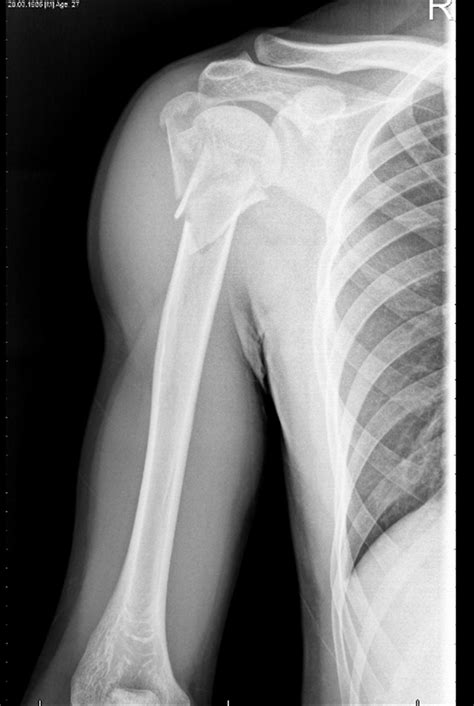

A proximal humerus fracture occurs at the top of the humerus, the long bone in the upper arm. This type of fracture is often the result of a fall onto an outstretched hand or a direct blow to the shoulder. The proximal humerus is composed of several parts, including the head, greater tuberosity, lesser tuberosity, and the surgical neck. Fractures can occur in any of these areas, and the severity can vary from minor cracks to complete breaks.

• Imaging Tests: X-rays are the primary imaging tool used to diagnose proximal humerus fractures. In some cases, additional tests such as CT scans or MRIs may be ordered to provide more detailed images.